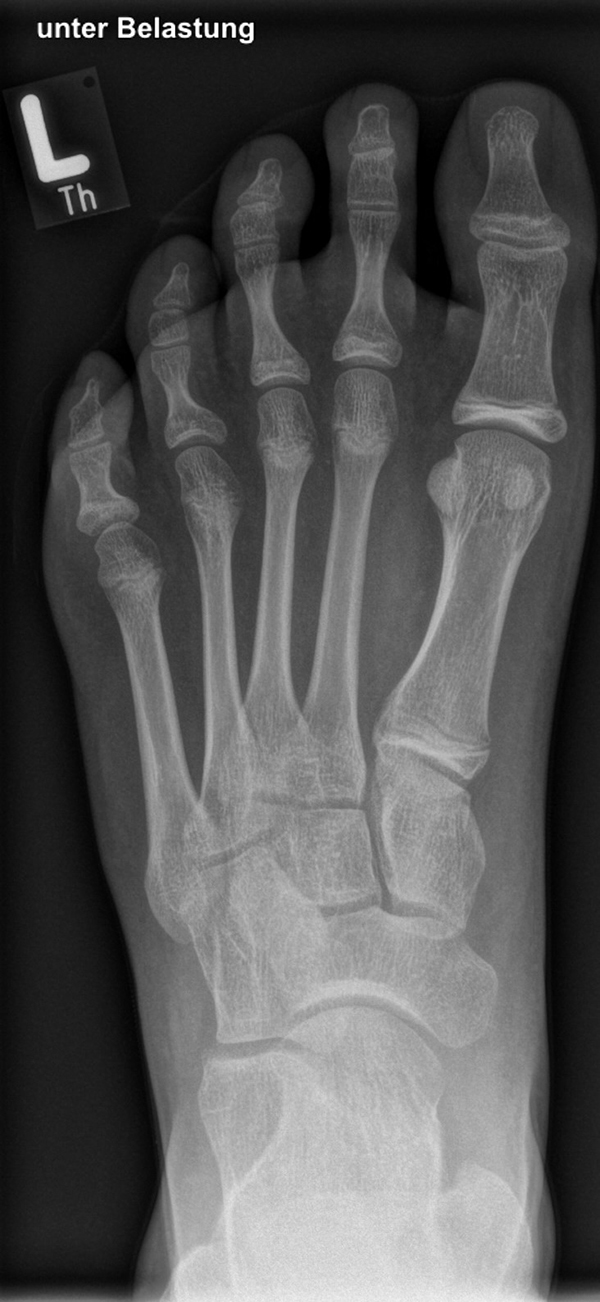

In der Korrektur des schmerzhaften, aber flexiblen Knick-Senk-Fußes oder Plattfußes ist die Schraubenarthrorise mit einem Sinus tarsi oder besser bezeichnet als Canalis tarsi Spacer und alternativ mit einer Calcaneus-Stopp-Schraube seit vielen Jahren ein etabliertes Verfahren und führt zu einer kompletten Korrektur von flexiblen Knick- und Plattfuß-Fehlstellungen (Abb. 7). Die nötige Schnittlänge über dem Sinus tarsi beträgt für beide Verfahren 1 cm.

Knick-Senk-Platt-Fuß Korrektur mit dem Canalis Tarsi Spacer